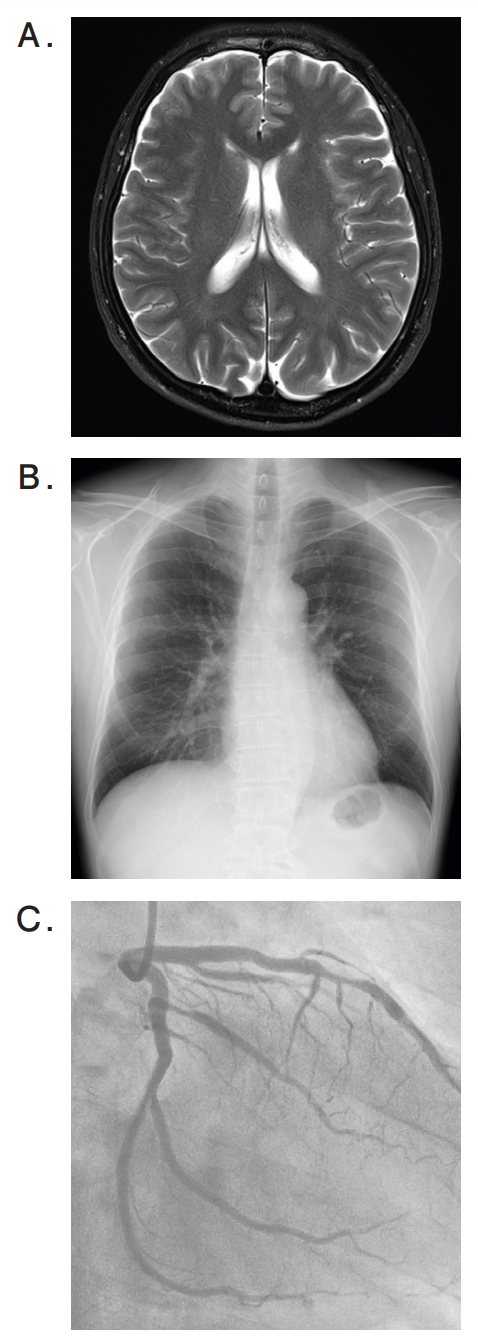

検査の画像を別に示す。

狭心症(angina pectoris)の手術に最も重要な検査はどれか。